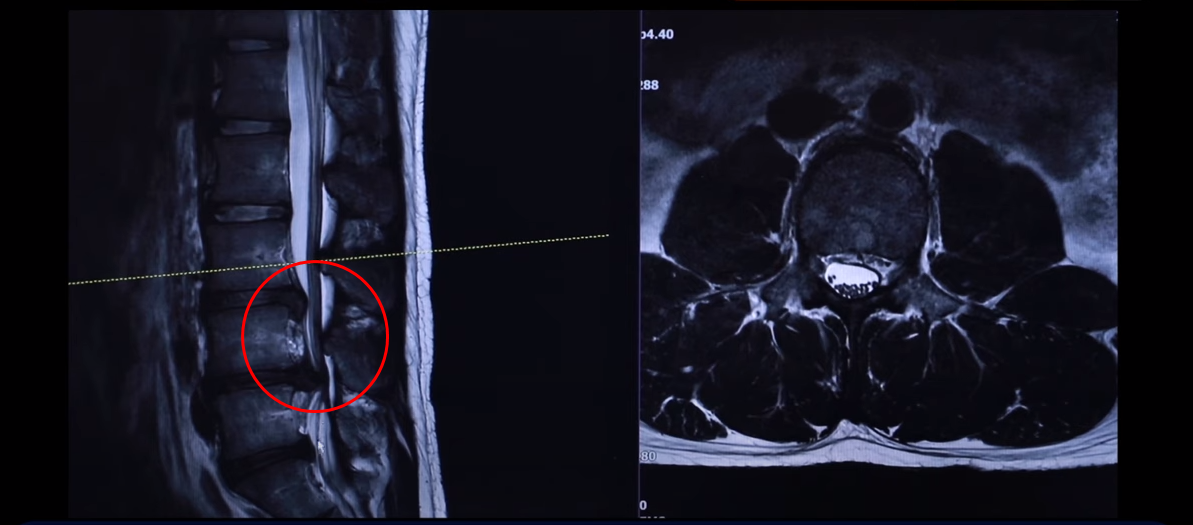

여기 24세 남자 환자분 MRI 보도록 하겠습니다. 옆에서 보는 MRI 보시다시피 어마어마하게 지금 심하게 터져 있습니다. 일반인이 보셔도 아실 정도로 두 마디가 아주 심하게 터졌고 여기도 약간 밀려 나와 있습니다.

왼쪽 다리에 참을 수 없을 정도로 심한 방사통이 생긴 겁니다. 이분이 디스크가 왜 터졌냐? 24살이신데 어릴 때부터 허리가 아팠습니다. 고등학교 때부터 오랫동안 허리가 아팠기 때문에 나이에 맞지 않게 세 마디가 벌써 퇴행돼 있죠. 군대 때도 아팠고 최근에 중량 스쿼트, 웨이트 트레이닝 하다가 디스크가 터지게 됩니다. 웨이트 트레이닝 하다가 다리가 이상한 걸 느껴서 병원에 가서 MRI를 찍어 보니까 이렇게 심하게 터져 있습니다. 보통 이렇게 심하게 터져 있으면 어느 병원을 가든 정형외과나 신경외과에서 수술을 해야 된다 이런 얘기를 들을 가능성이 있습니다.